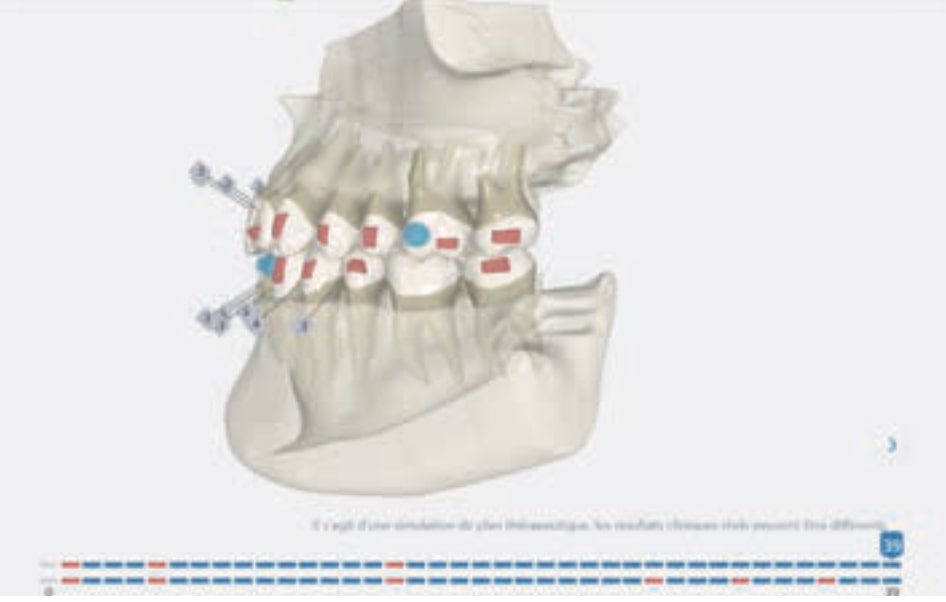

- Distalization of the Third and Fourth Quadrants: Move the teeth distally in these quadrants to achieve a Class I relationship using the A8 protocol, improving the patient’s dental alignment and occlusion.

Treatment setup